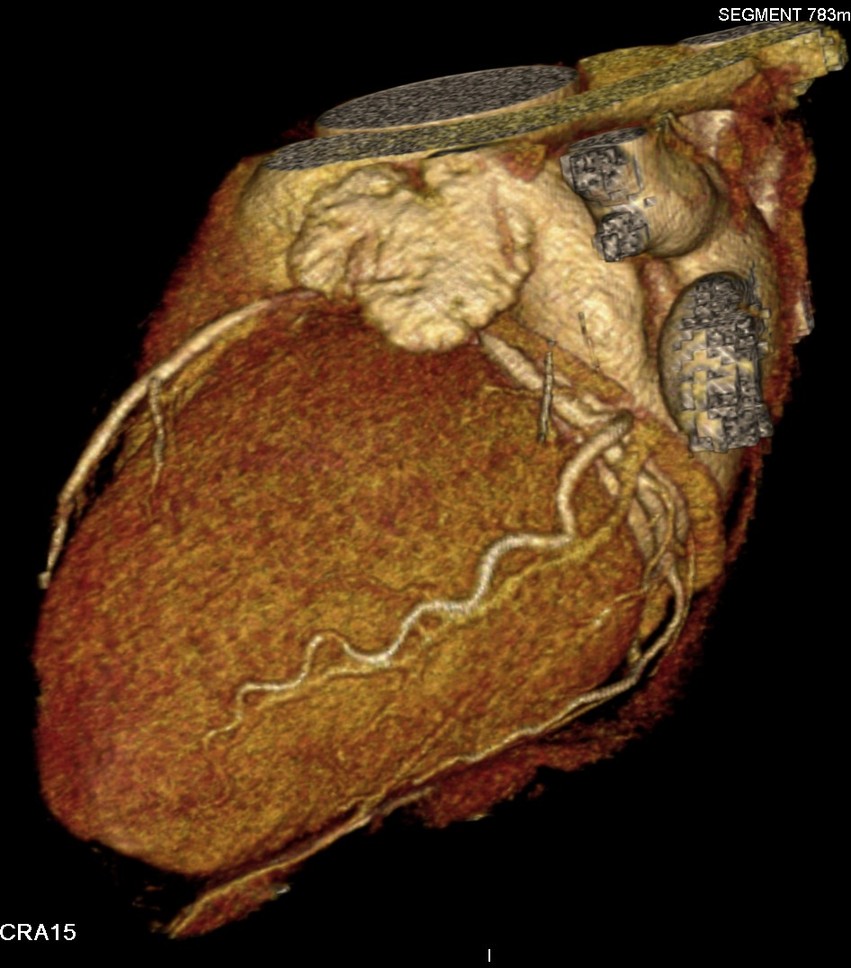

标题: CT24400:患者54岁,心前区不适进行心脏冠脉造影检查。 [打印本页]

标题: CT24400:患者54岁,心前区不适进行心脏冠脉造影检查。

患者54岁,心前区不适进行心脏冠脉造影检查。高手看看有问题没有?

图像很漂亮,好像未见异常